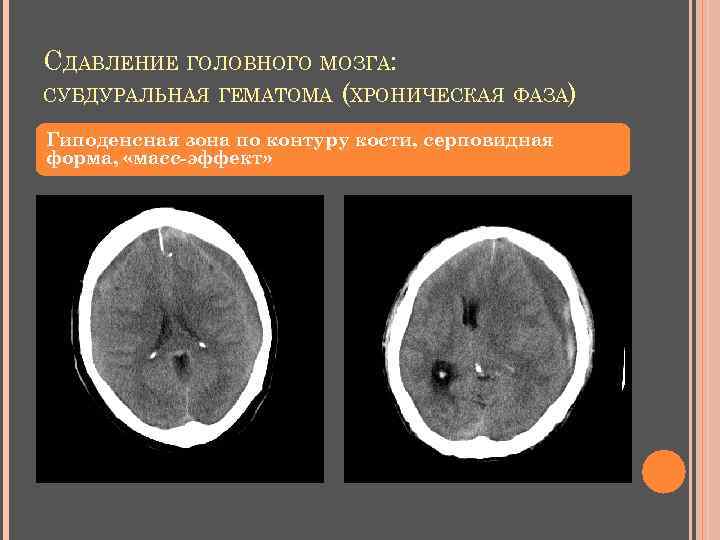

СУБДУРАЛЬНАЯ ГЕМАТОМА Острая: Подострая: форма серпа гиперденсная неровный внутренний контур утрачивает форму серпа становится изоденсной приобретает капсулу нарастает «масс-эффект» Хроническая: от 1 до 4 нед. : двояковыпуклая гиподенсная или изоденсная капсула «масс-эффект»

СДАВЛЕНИЕ ГОЛОВНОГО МОЗГА: СУБДУРАЛЬНАЯ ГЕМАТОМА (ХРОНИЧЕСКАЯ ФАЗА) Гиподенсная зона по контуру кости, серповидная форма, «масс-эффект»